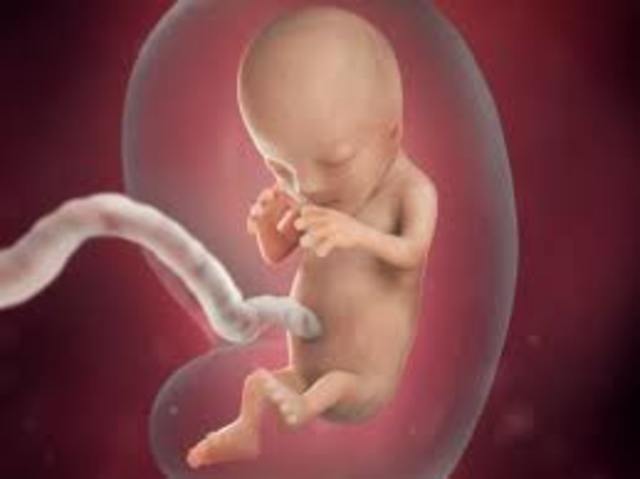

• development at 12 weeks

development at 12 weeks

the baby measures 2 inches and starts to make its own movements you may start too feel the top of the uterus above your public bone